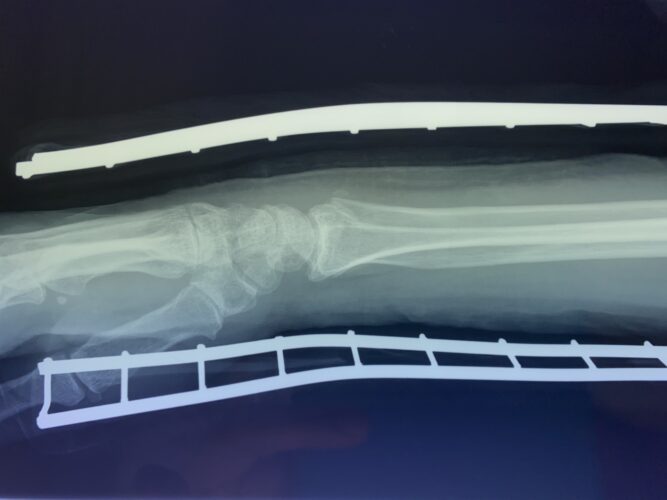

さわやか千葉県民プラザ(前腕骨下端部骨折)

春日部市市民活動センター(前腕骨骨幹部骨折)

第26回整骨研究会「賜恩」研修会開催